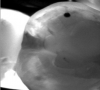

As an adjunct to 2-dimensional digital radiography systems, the use of 3-dimensional radiographs can present an attractive option. A CBCT system can be used to produce a 3-dimensional image to enhance or augment diagnostic capabilities.3 While adherence to the ALARA (as low as reasonably achievable" principle for all ionizing radiation modalities is the clear best practice to minimize patient radiation exposure, CBCT units impart doses approximately the same as 2-dimensional digital units, and indeed all digital imaging technology for oral healthcare produce far less exposure than medical CT units.3 When used as appropriately indicated, both 2-dimensional and 3-dimensional digital radiographic technology provide practitioners access to oral and maxillofacial information that can be beneficial in the diagnosis of osseous degradation, root pathologies, fractures, and pathologies, as well as the aforementioned capacity to expand into implant surgical, orthodontic, or endodontic procedures.3-5

Transilluminating technologies emit light at the base of the tooth at the gingival area and transmit light up through the tooth. At the applied wavelength, enamel starts to absorb fewer photons and water starts to absorb more photons, so lesions appear as dark areas on a monitor.6-8 This visualization can be helpful not only for the clinician to identify and diagnose problematic areas (Figure 1), but it also allows patients to see all aspects of their mouth including their cheek, tongue, and tooth, as well as the areas that have decay, thereby potentially assisting in case acceptance.

Transillumination can be used in interproximal, occlusal, and anterior surfaces.5 In many cases the technology is able to show how expansive the decayed area is on occlusal areas that may only have a minimal pit that would not allow a probe to be used (Figure 2 through Figure 4). Visualizing the interproximal regions of posterior teeth is possible as well although this may require a specialized fiber-optic tip.6